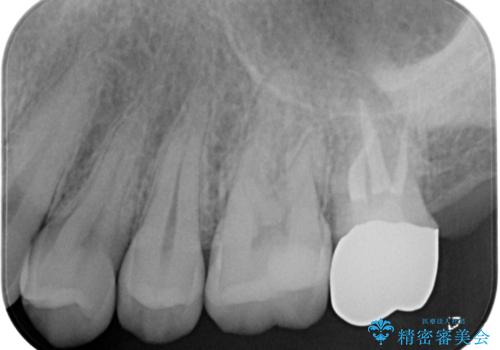

適合の良い被せ物が入りました。

ゴールドの被せ物は適合がよく虫歯の再発のリスクが低くなります。

また根の治療を行う時はラバーダムを行い治療しています。